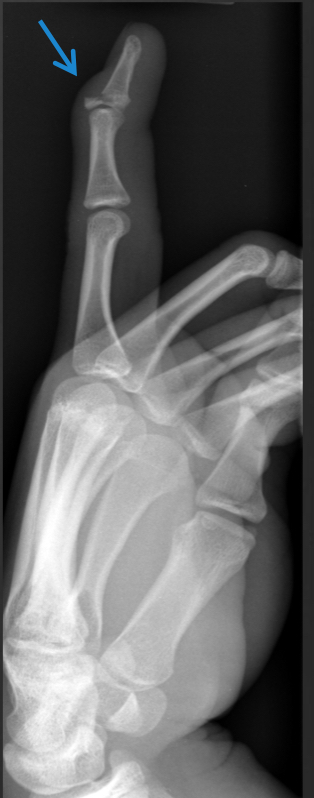

what views are mandatory in long boned which ones are alternative

Always at least AP, Lateral (orthogonal views - 90°) Oblique is initial 3rd view (hand, wrist, ankle, foot, etc) ○ Special views

sunrise view of the patella

3 special views ordered

● Perpendicular - axial plane (sunrise and axial)